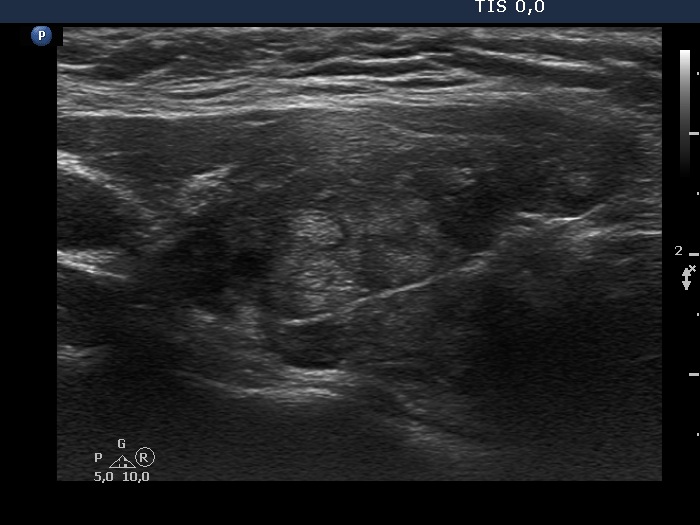

Discrete lesion or nodule in Hashimoto's thyroiditis - case 29 (1125) (ultrasonographic picture 3)

Right lobe, another longitudinal view. This section reveals an area with pseudolobular pattern.